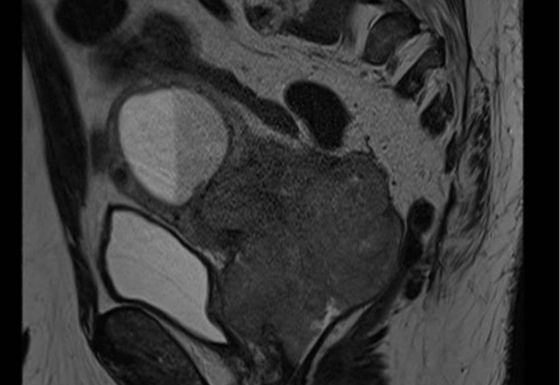

The patient was treated in October 2018 with radical radiotherapy receiving 74 Gy in 37 fractions. He had a good biochemical response, with a PSA nadir of 0.08. In 2021, his PSA started to rise and reached 2.73. A PSMA PET scan showed PSMA avid local recurrence in the prostate only. He started on LHRH agonist but was experiencing extreme lethargy and hot flushes which had a significant impact on his QOL and difficulty in tolerating treatment.

Figure 1: MR and PSMA PET fusion showing recurrence

Figure 2: Contouring target lesion

Figure 3: radiotherapy plan axial view

Figure 4: Radiotherapy plan 3D view